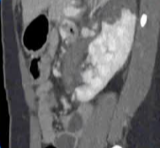

弹簧栓子的位置:胰大动脉和胰背动脉之间

|

白色细箭头:胰背动脉

白色粗箭头:胰横动脉

短黑箭头:血液流动方向

※:弹簧栓子 |